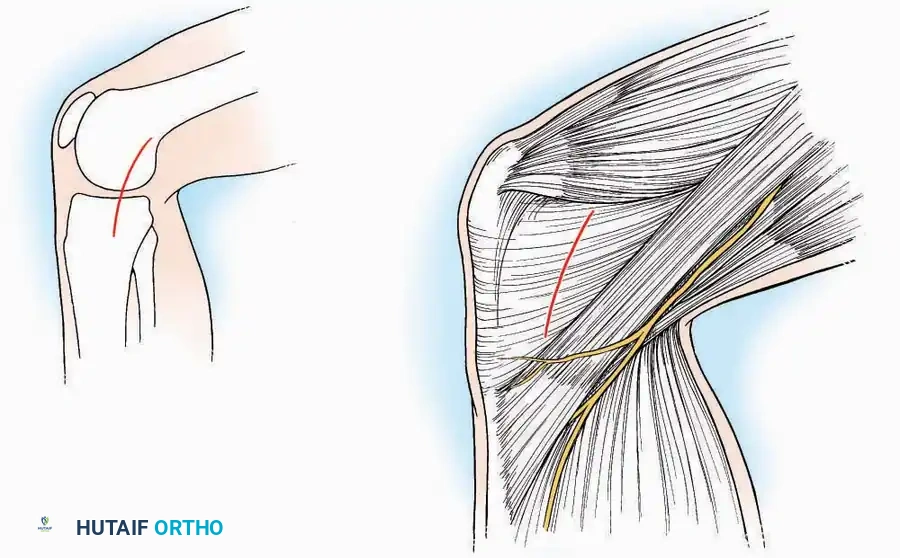

Anterolateral Approach

The anterolateral approach is widely considered the "universal incision" for the foot and ankle. It provides unparalleled access to the ankle joint, the talus, and the majority of the tarsal articulations, while safely avoiding the major anterior neurovascular bundle. The only tarsal joints inaccessible via this route are the naviculocuneiform joints (specifically the medial and intermediate).

Indications: Total talectomy, triple arthrodesis, ankle arthrodesis, and open reduction of complex talar neck fractures.

Surgical Technique:

* Incision: Begin over the anterolateral aspect of the leg, medial to the fibula and 5 cm proximal to the ankle joint line. Carry it distally over the joint, crossing the anterolateral aspect of the talar body and the calcaneocuboid joint, terminating at the base of the fourth metatarsal.

* Superficial Dissection: Incise the superficial fascia and the superior and inferior extensor retinacula down to the periosteum of the tibia and the ankle joint capsule.

* Vascular Ligation: This trajectory usually requires the identification and ligation of the anterolateral malleolar and lateral tarsal arteries.

* Nerve Protection: Retract the skin edges carefully. Identify and protect the intermediate dorsal cutaneous branches of the superficial peroneal nerve (SPN), which frequently cross the distal aspect of this incision.

* Muscle Management: Identify the origin of the extensor digitorum brevis (EDB) muscle on the lateral calcaneus. Divide it in the direction of its fibers, or detach its origin entirely and reflect it distally to expose the subtalar and calcaneocuboid joints.

* Deep Exposure: Retract the extensor digitorum longus (EDL) tendons, the dorsalis pedis artery, and the deep peroneal nerve (DPN) medially. Incise the anterior ankle capsule to expose the tibiotalar joint.

* Tarsal Exposure: Expose the talonavicular joint by dissecting deep to the extensor tendons and incising its capsule transversely. Continue laterally through the capsule of the calcaneocuboid joint. By excising the fat pad within the sinus tarsi (lateral and inferior to the talar neck), the posterior facet of the subtalar joint is brought into direct view.